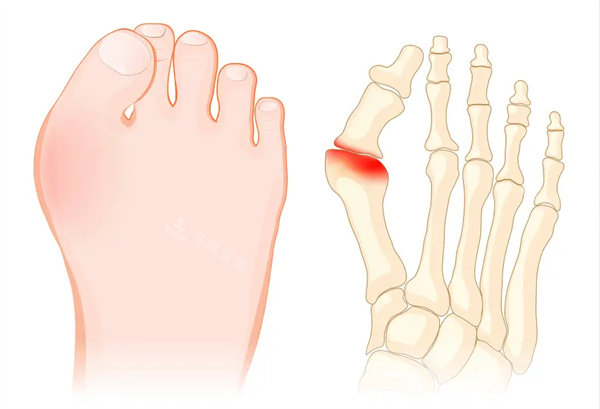

大脚骨,医学上称为拇外翻,是一种常见的足部畸形问题。它不仅影响脚部的美观,还给患者的日常生活带来诸多不便。对于许多患有大脚骨的人来说,走路时的疼痛是更直接的困扰。

在外观方面,大脚骨使得脚趾形态变得怪异,这让很多患者在选择鞋子时受到极大限制。